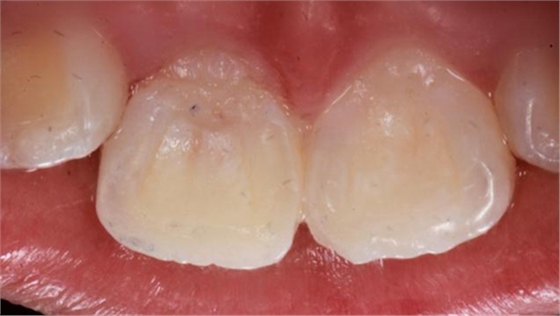

第二日復(fù)查,給予樹(shù)脂恢復(fù)A2A1B1切斷缺損。術(shù)后如下圖: